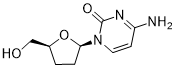

馬鞍山致研生物醫(yī)藥科技有限公司成立于馬鞍山市鄭浦港新區(qū)現(xiàn)代產(chǎn)業(yè)園。公司專(zhuān)注于生物小分子、醫(yī)藥中間體相關(guān)產(chǎn)品的研發(fā)和生產(chǎn),產(chǎn)品主要包括DNA亞磷酰胺單體、RNA亞磷酰胺單體、特殊單體以及按照客戶(hù)要求定制的RNA和DNA,并且公司提供定制合成等方面的研究服...

馬鞍山致研生物醫(yī)藥科技有限公司成立于馬鞍山市鄭浦港新區(qū)現(xiàn)代產(chǎn)業(yè)園。公司專(zhuān)注于生物小分子、醫(yī)藥中間體相關(guān)產(chǎn)品的研發(fā)和生產(chǎn),產(chǎn)品主要包括DNA亞磷酰胺單體、RNA亞磷酰胺單體、特殊單體以及按照客戶(hù)要求定制的RNA和DNA,并且公司提供定制合成等方面的研究服...